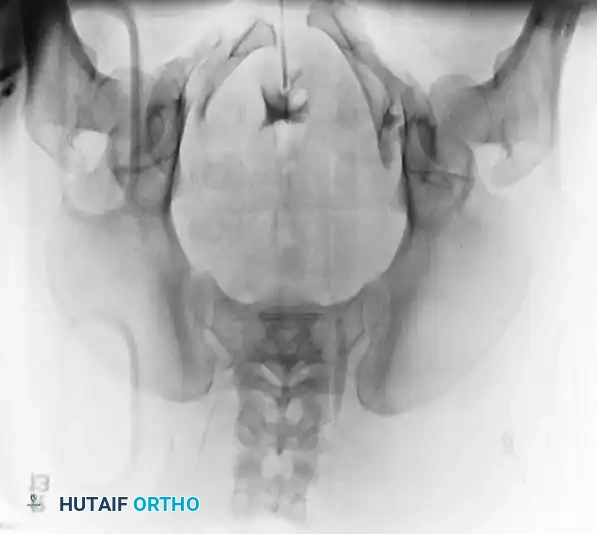

2. Symphyseal Plating (Anterior Ring)

• Positioning: Supine on a radiolucent table.

• Reduction: A Weber clamp or specialized pelvic reduction forceps are placed on the pubic tubercles or via drill holes in the superior rami to reduce the diastasis.

• Fixation: A multi-hole, stout pelvic reconstruction plate (typically 4 to 6 holes) is placed superiorly. Screws must be directed carefully to avoid joint penetration or bladder injury.

Image